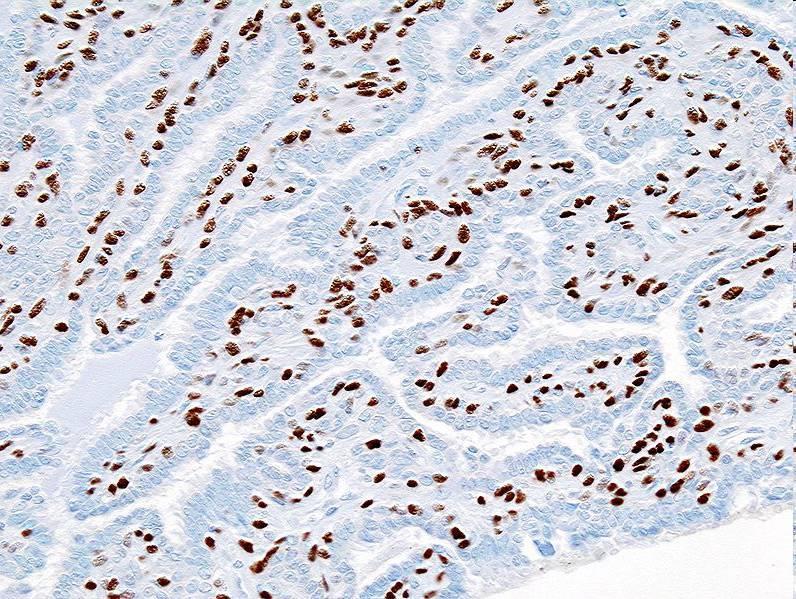

5-14% of breast carcinomas High incidence of multifocal and bilateral disease Tumour cells may show mucin filled vacuoles E-cadherin negative

E-cadherin